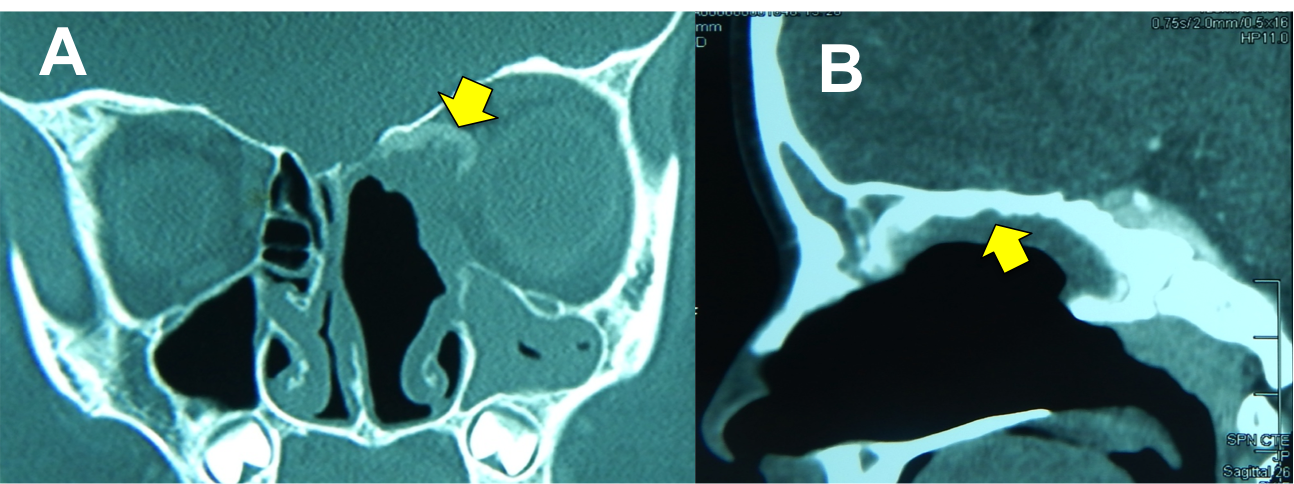

Introducción: La cirugía endoscópica endonasal se ha convertido en una herramienta fundamental para el manejo de patologías que comprometen la base de cráneo. En casos bien seleccionados, estas técnicas permiten resecciones quirúrgicas con una menor morbilidad sin comprometer los principios oncológicos de resección. Con el desarrollo de instrumental especializado, nuevas tecnologías y la experiencia de los cirujanos, la cirugía endoscópica endonasal se usa cada vez más en cirugía de base de cráneo en niños.

Resultados: Fueron intervenidos 8 pacientes entre los 2 y 14 años, con una edad promedio de nueve años y un seguimiento promedio de 16 meses. En el 75% se hizo una resección total del tumor. Un paciente requirió una reintervención y un paciente fue sometido a radiocirugía post-operatoria. 1 paciente falleció a pesar de múltiples intervenciones, quimioterapia y radioterapia.

Conclusión: La cirugía endoscópica endonasal para tumores de base de cráneo puede ser utilizada de forma segura en los pacientes pediátricos, es una técnica que en casos bien seleccionados pueden ofrecer excelentes resultados disminuyendo la morbilidad y complicaciones de las técnicas abiertas.